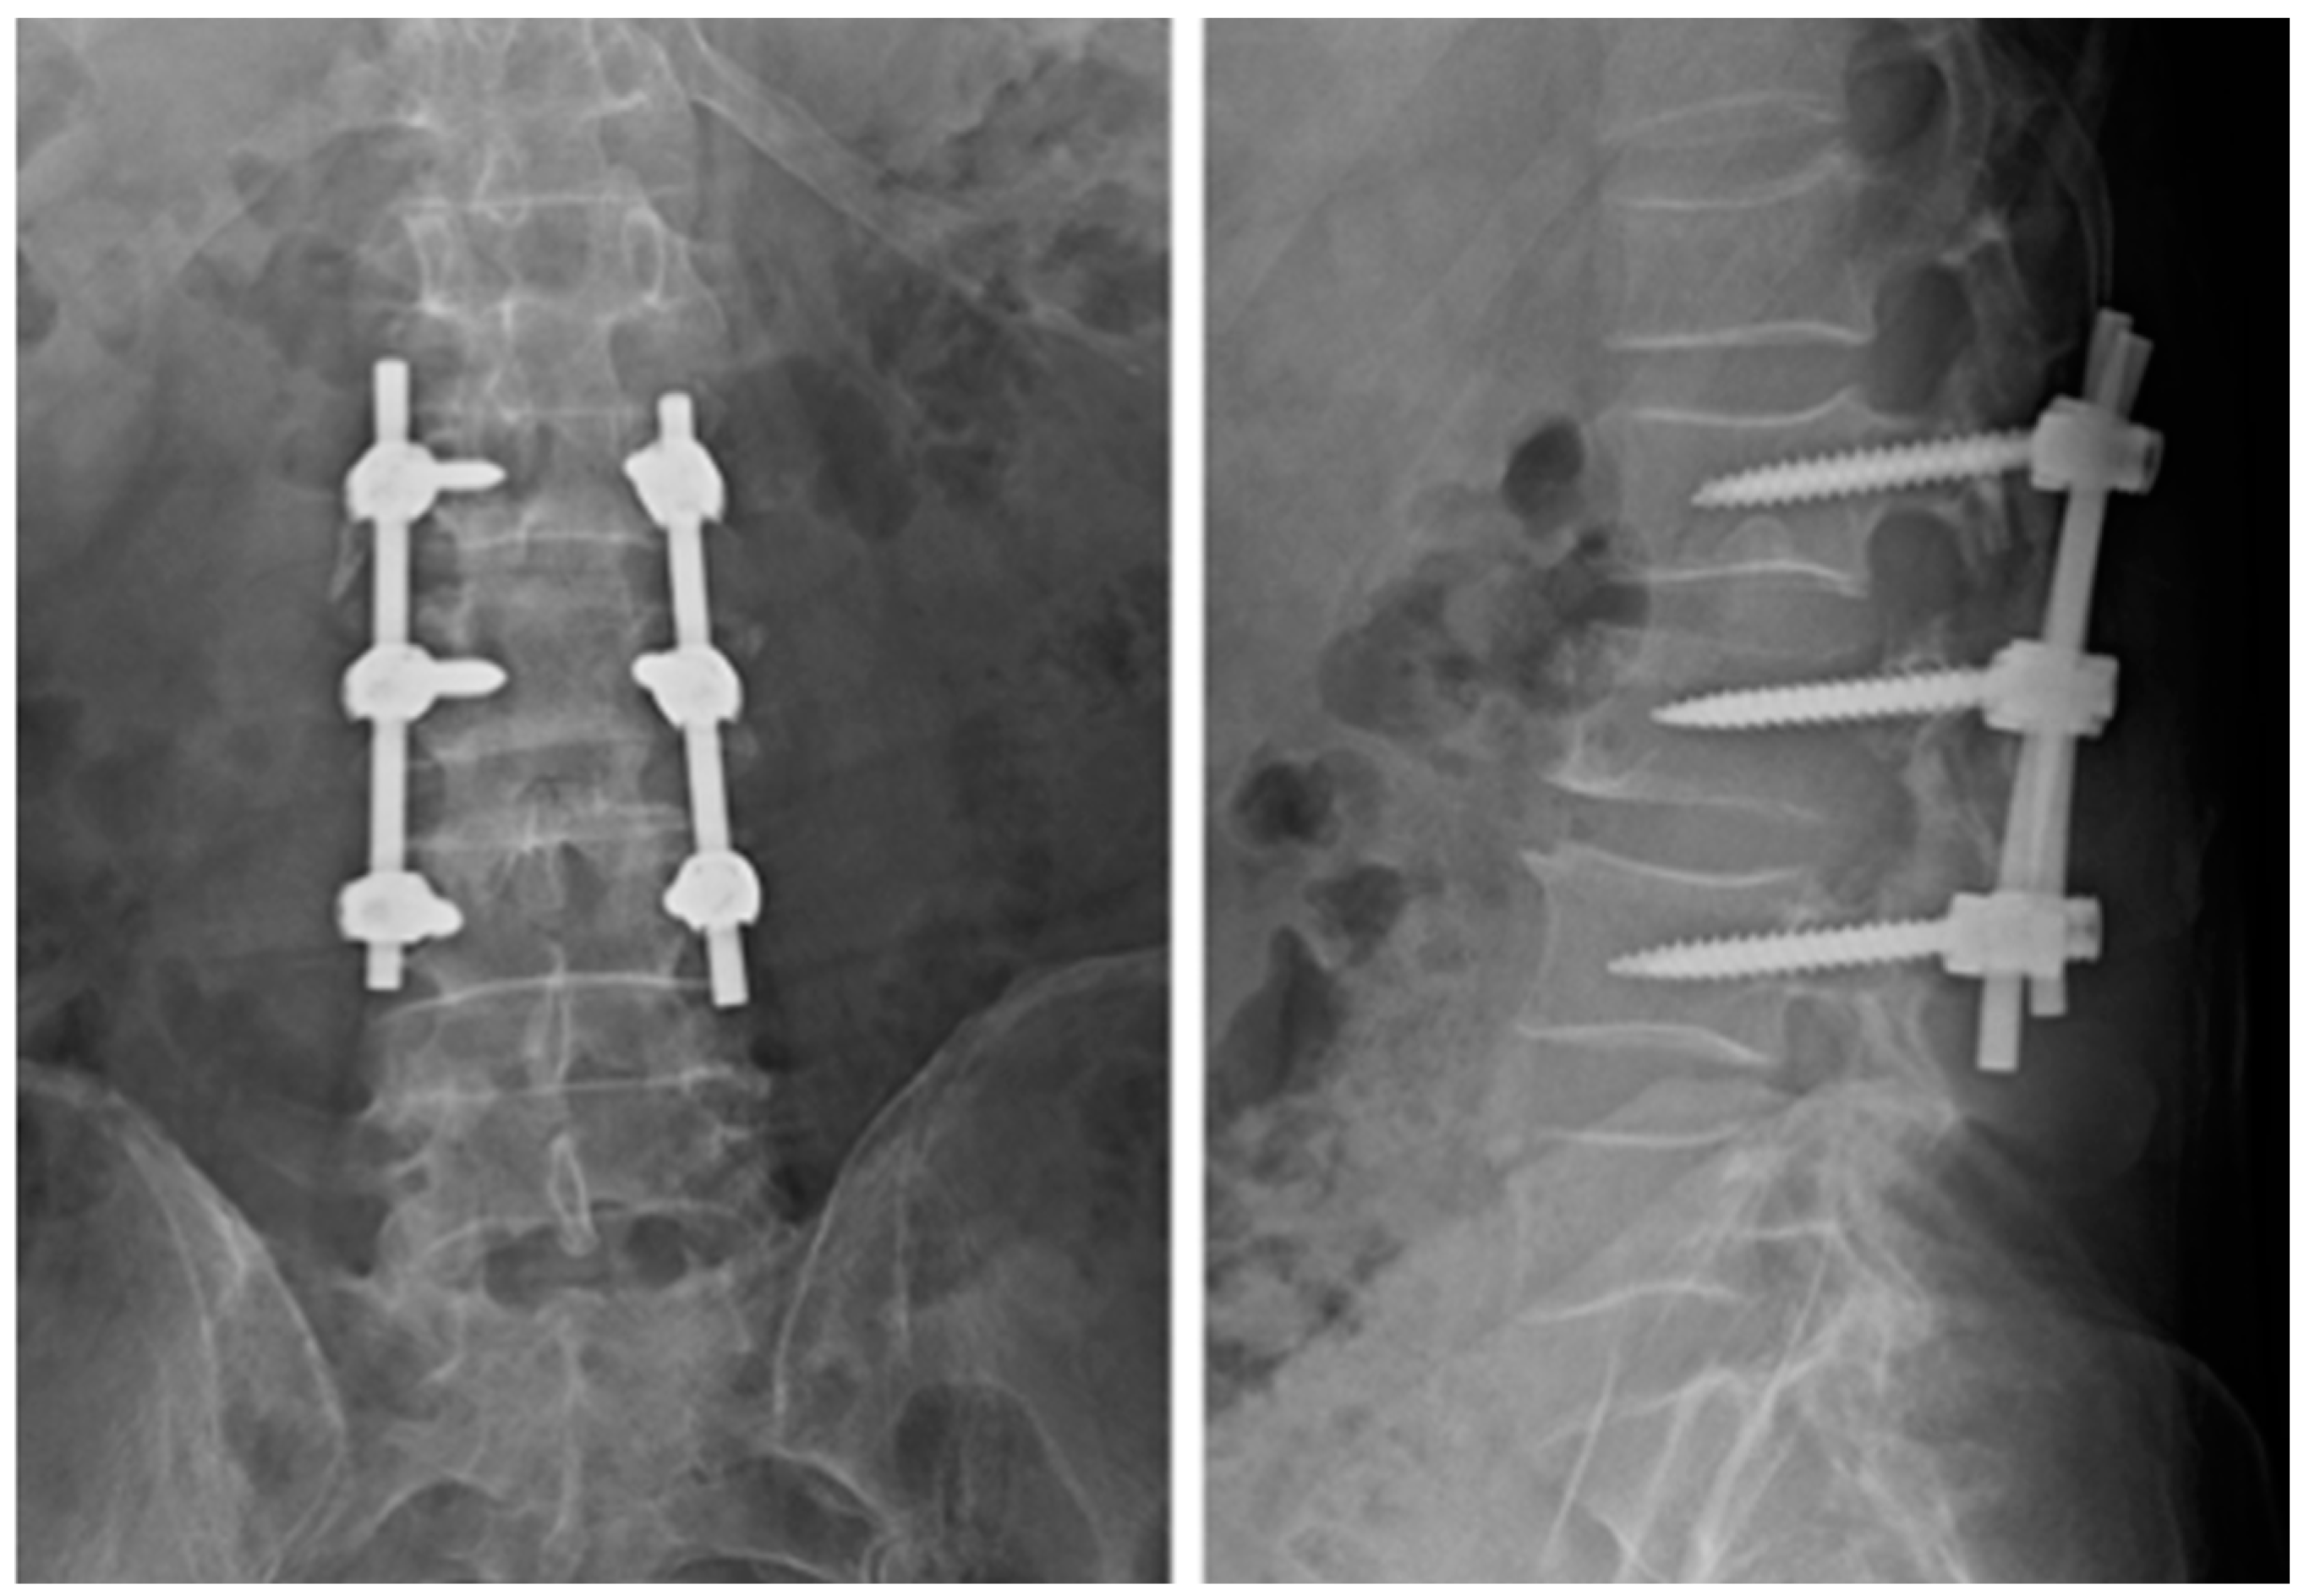

Follow-up assessments, comprising both clinical and radiological examinations, were scheduled at one- and four-week post-surgery, followed by three-month intervals thereafter. The evaluation of the patient’s reported outcomes using the Visual Analog Scale (VAS) revealed a statistically significant reduction from 10 to 2 (p < 0.001). However, no significant changes were noted in the patient’s neurological status, and there were no local or general side effects observed either immediately after waking or during postoperative follow-up. Imaging restaging conducted 3 months after surgery (Figure 5) demonstrated no signs of implant loosening, and the size of the tumor at the L3 vertebra remained stable. Unfortunately, the patient passed away at 4 months of follow-up due to respiratory failure caused by the progression of metastatic disease to the lungs.

Figure 5.

Case 1. Radiographs taken 3 months after surgery demonstrate no signs of implant loosening.